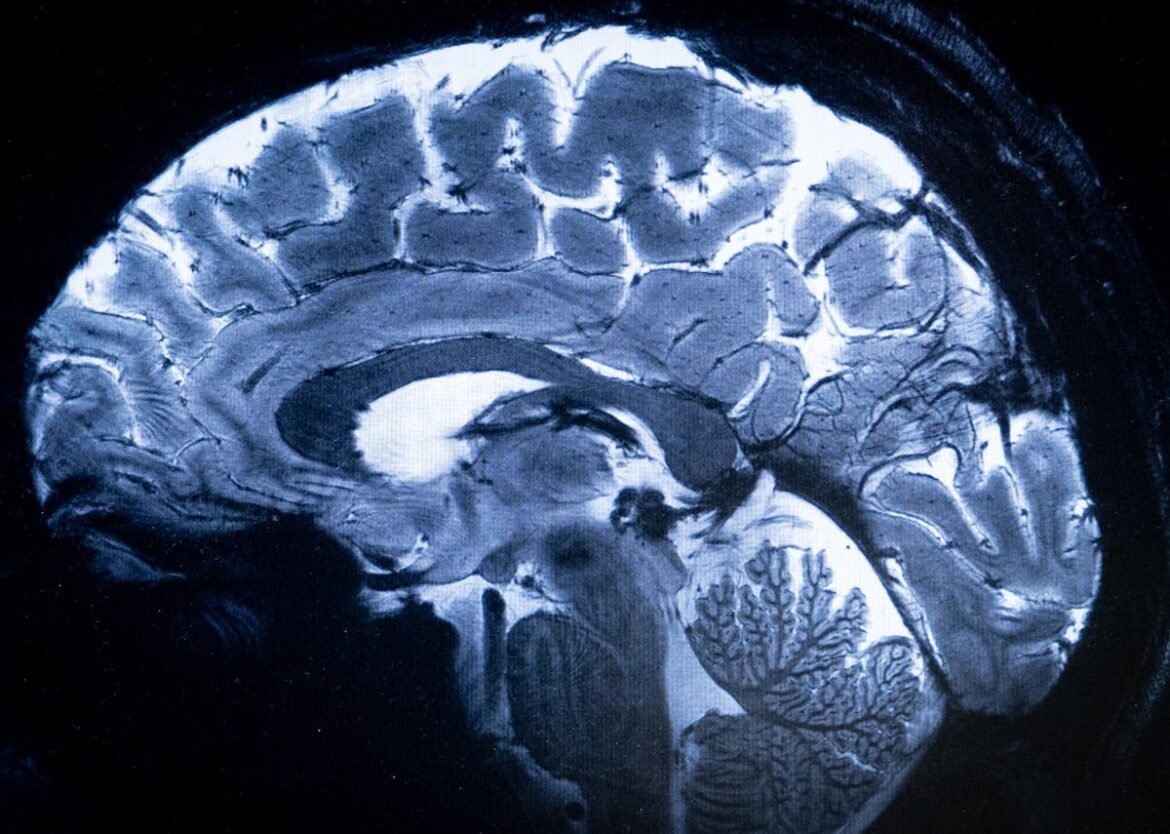

An MRI image of the human brain.

Alain Jocard/AFP via Getty Images